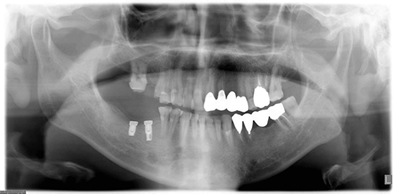

● インプラント治療の症例